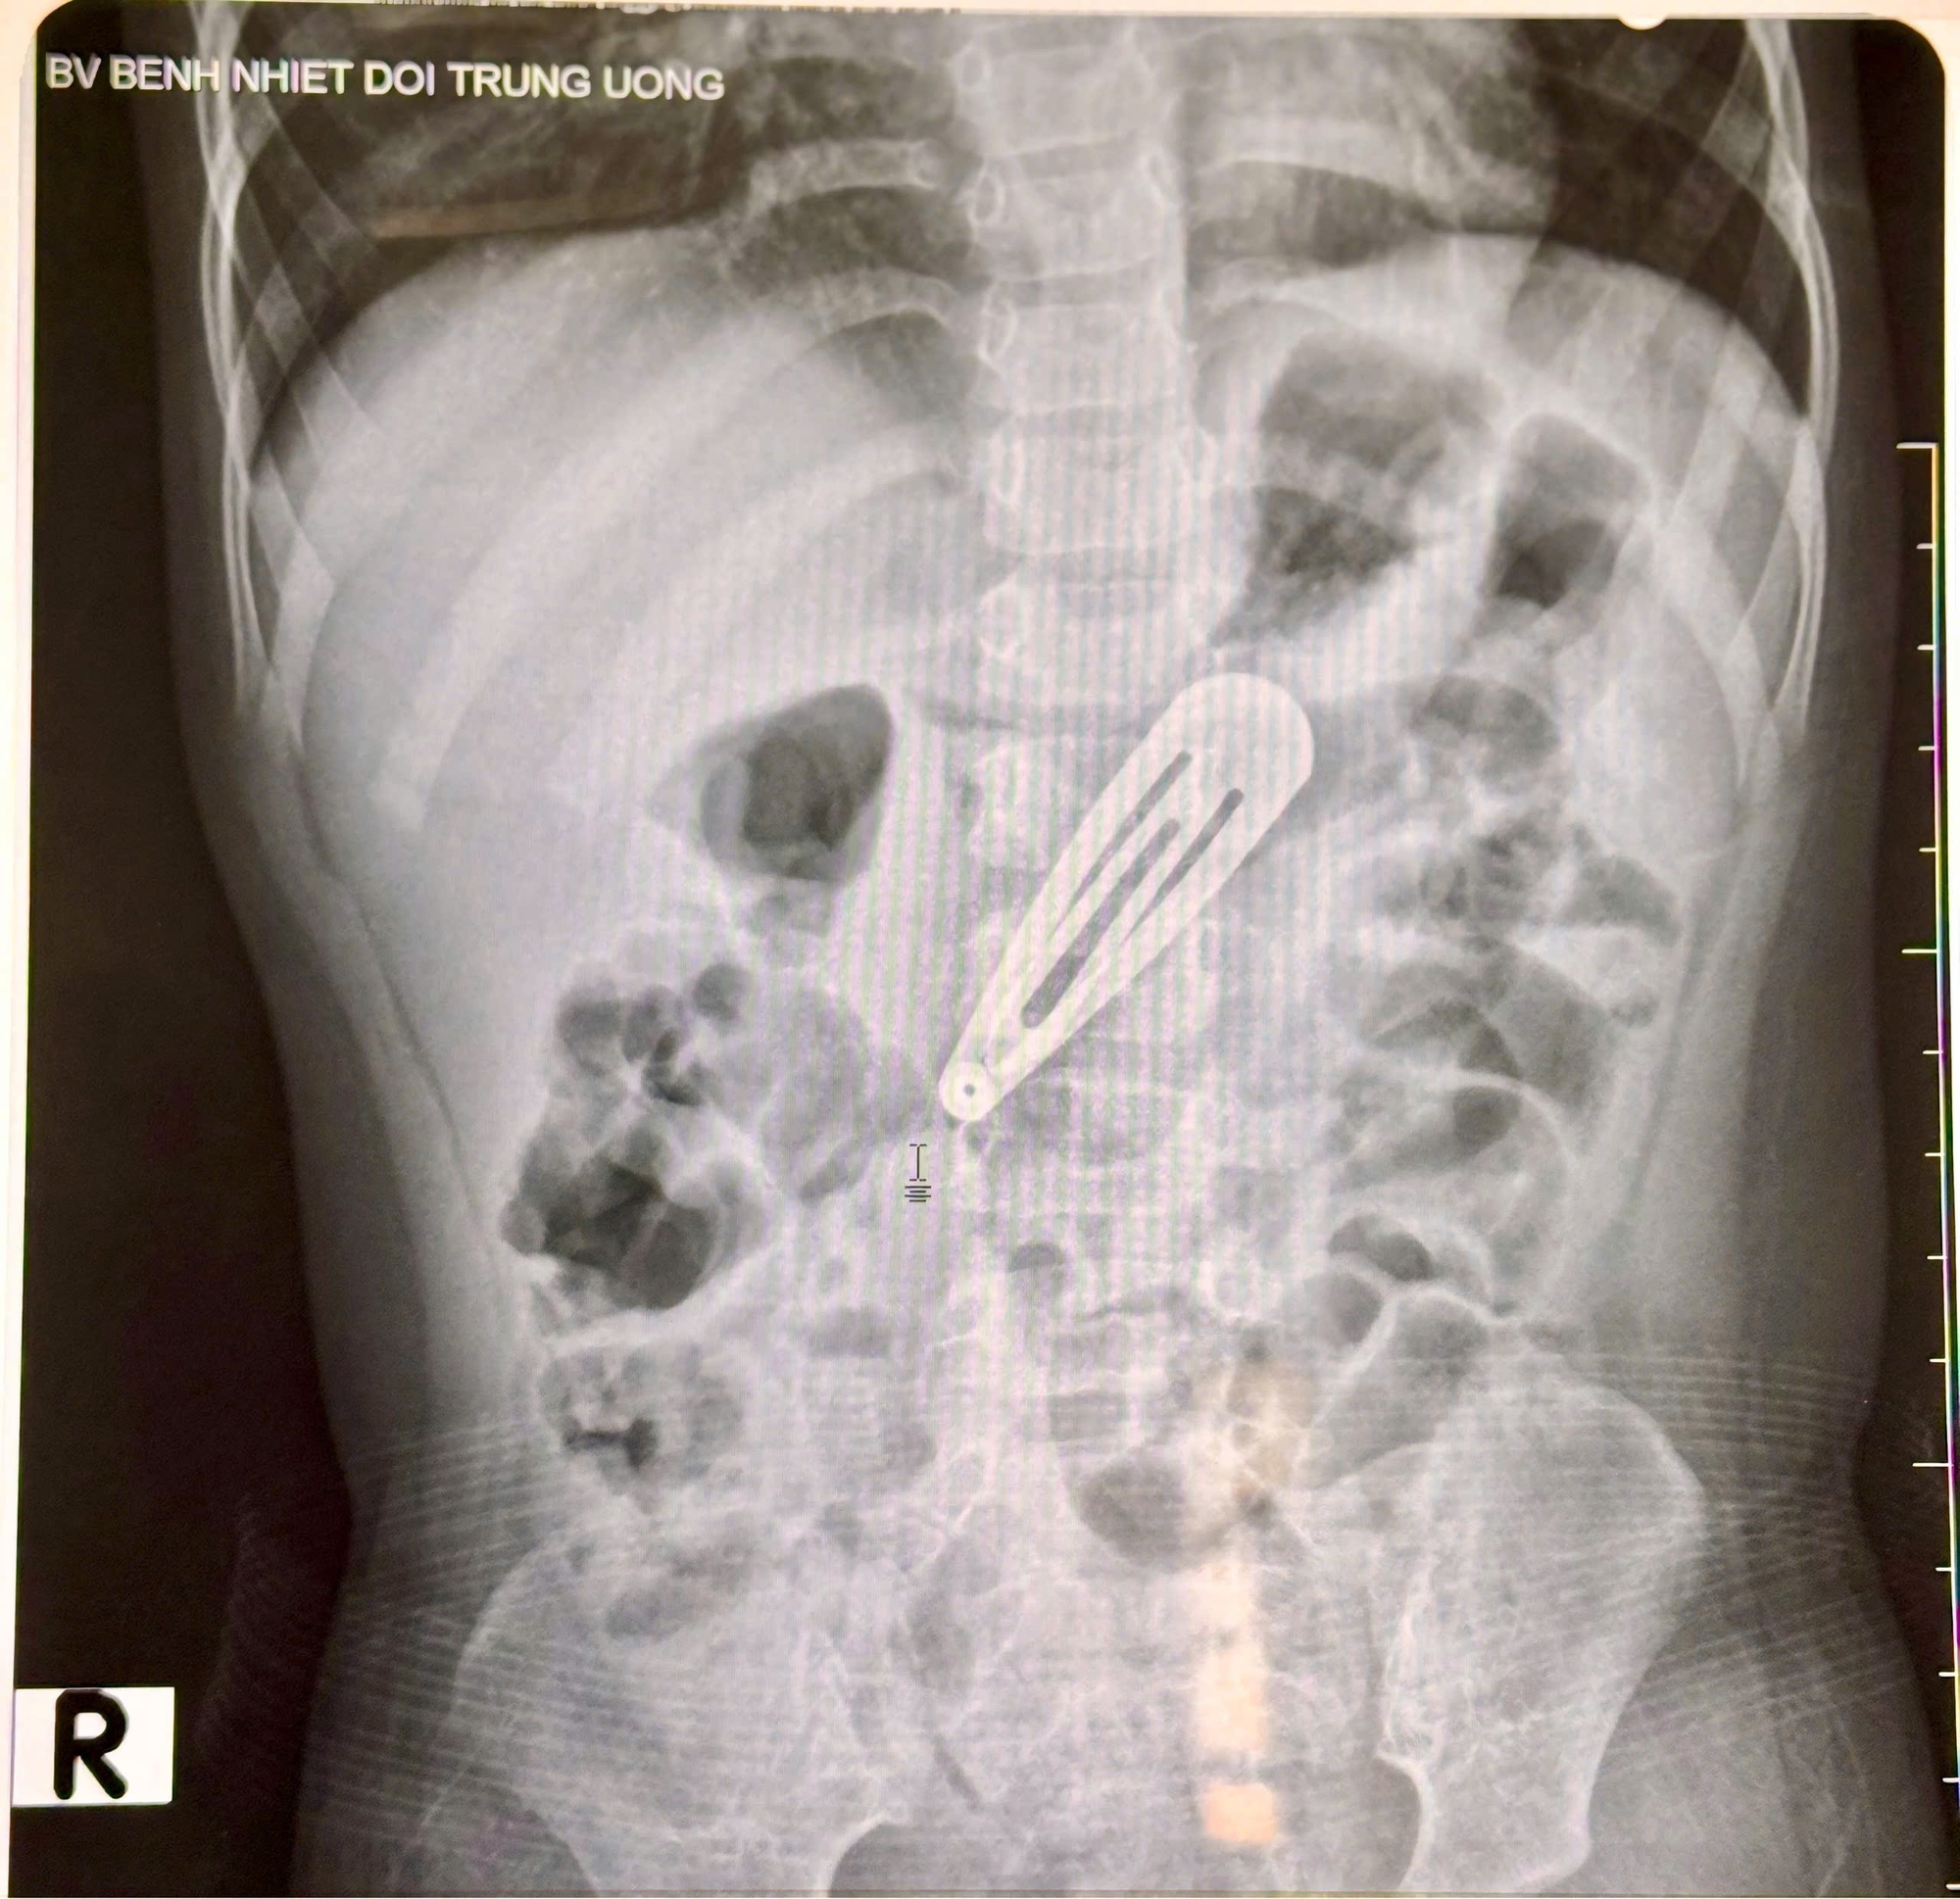

Sau khi thăm khám lâm sàng và chụp X-quang bụng, các bác sĩ ghi nhận hình ảnh một dị vật kim loại nằm trong ổ bụng, tương ứng vị trí dạ dày của bé. Bé nhanh chóng được chuyển sang Trung tâm Nội soi tiêu hóa và Thăm dò chức năng để tiến hành nội soi can thiệp lấy dị vật ra ngoài.

Hà Nội: Bé gái 21 tháng tuổi nhập viện vì trẻ nhỏ nuốt dị vật kẹp tóc kim lọai - Ảnh 2.

Hình ảnh chụp x-quang